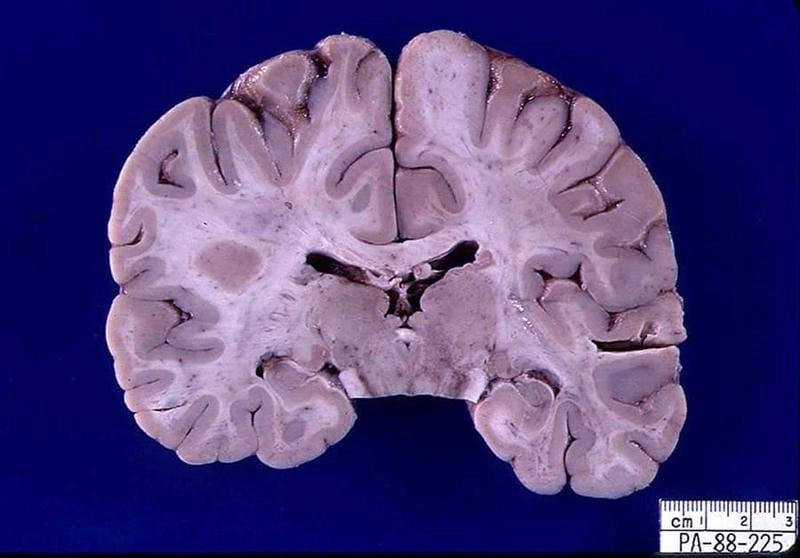

Brain scan showing what is La Crosse encephalitis